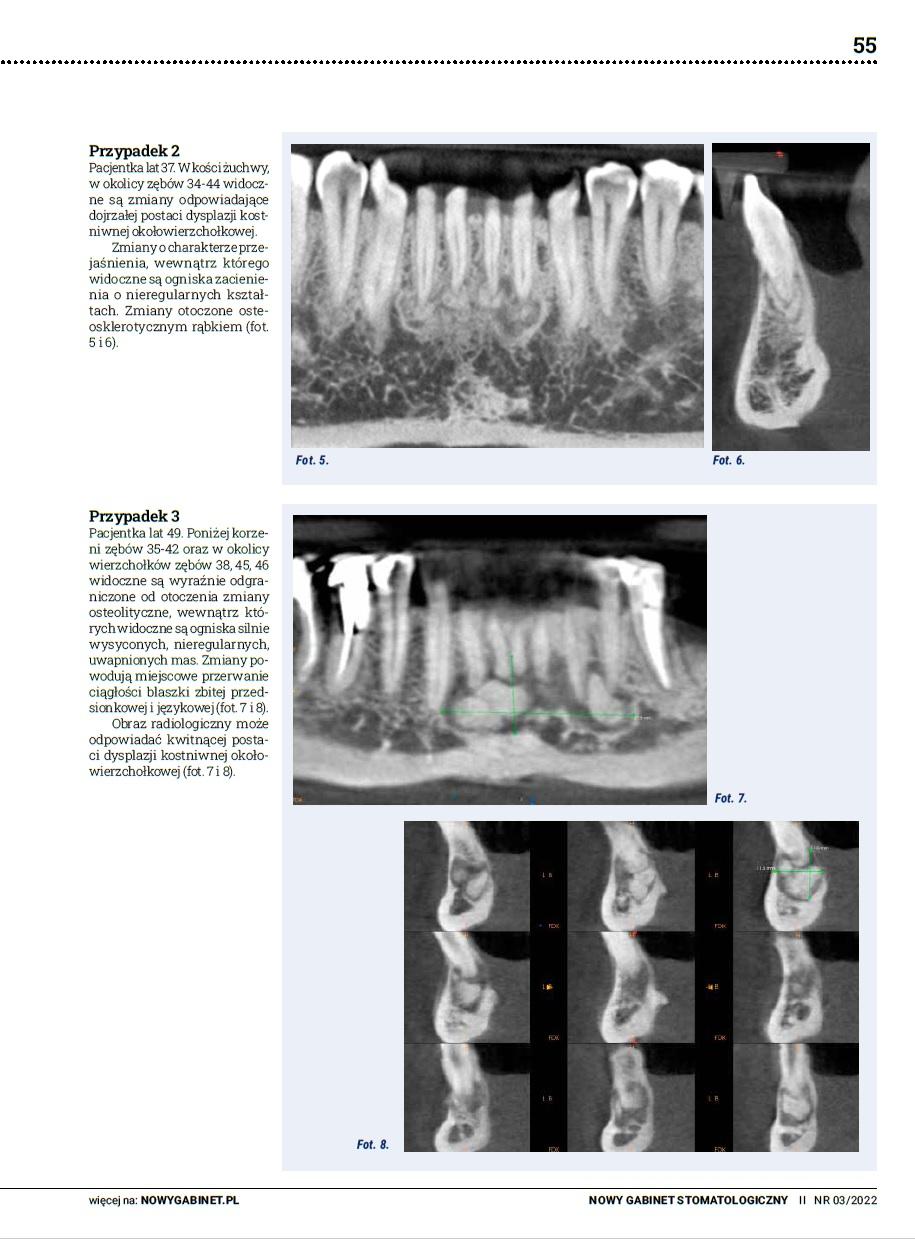

Pułapka diagnostyczna: dysplazja kostniwno-kostna